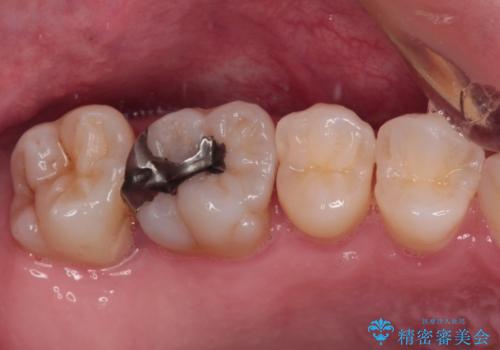

また、奥歯の銀歯をゴールドにしたいとのことで、並行してPGAインレーにて修復治療を行うこととしました。